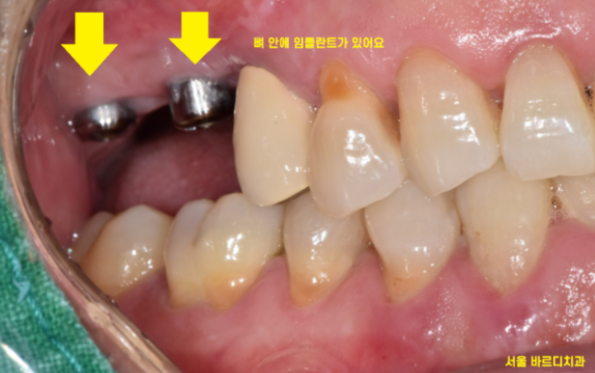

경우에 따라 잇몸 뼈가 많이 부족한 경우

잇몸 안에 임플란트를 묻어둬야 할 경우가 있습니다.

이럴 경우 묻어둔 임플란트를 잇몸 밖으로 노출 시키는

2차 수술이 필요한데요.

잇몸 안에 임플란트를 묻어 둔 경우

임플란트 수술한게 맞냐는 질문을 많이들 해주십니다.

그도 그럴 것이 사진과 같은 모습이기 때문이죠~!

잇몸밖에 안보이죠~?

뼈 사진을 보시게 되면

임플란트 잘 심겨져 있답니다.